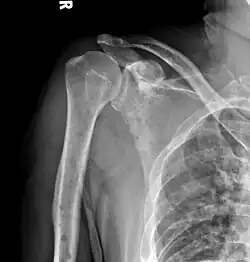

The diagnostic examination of a person with suspected multiple myeloma typically includes a skeletal survey. This is a series of X-rays of the skull, axial skeleton, and proximal long bones. Myeloma activity sometimes appears as "lytic lesions" (with local disappearance of normal bone due to resorption) or as "punched-out lesions" on the skull X-ray ("raindrop skull"). Lesions may also be sclerotic, which is seen as radiodense.[76] Overall, the radiodensity of myeloma is between −30 and 120 Hounsfield units (HU).[77] Magnetic resonance imaging is more sensitive than simple X-rays in the detection of lytic lesions. An MRI may supersede a skeletal survey, especially when vertebral disease is suspected. Occasionally, a CT scan is performed to measure the size of soft-tissue plasmacytomas. Nuclear Medicine Bone scans are typically not of any additional value in the workup of people with myeloma (no new bone formation; lytic lesions not well visualized on nuclear bone scan).

X-ray of the forearm, with lytic lesions -

Humerus with multiple myeloma lesions -

Same humerus before, with just subtle lesions